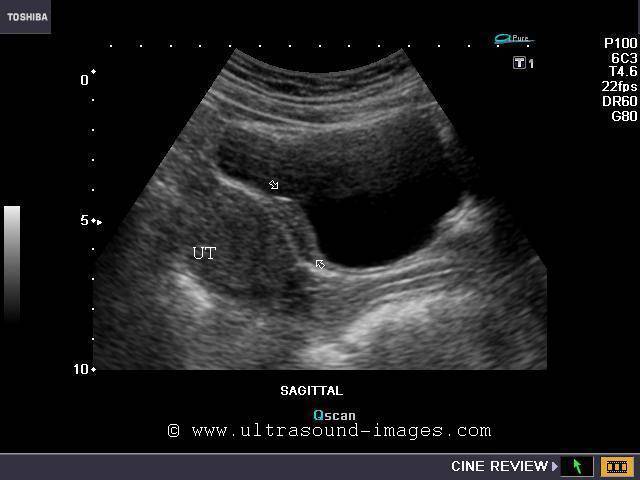

Asherman's syndrome: Uterine synechiae

This young adult female patient underwent D &C (dilatation and curettage) some time ago. Presently, she presented with abdominal pain. The sagittal ultrasound images of the uterus show small amount of fluid inside the endometrial cavity with adhesions between the anterior and posterior walls of the cavity (arrowheads). These ultrasound findings are diagnostic of Asherman's syndrome or uterine synechia/ adhesions. Synechiae of the uterus are typically seen following a D & C of the uterus. The cause is possibly adhesions or scarring within the walls of the raw surfaces of the uterine cavity. This condition is usually treated by surgical intervention, using a procedure called adhesiolysis during hysteroscopy. Untreated, this condition can result in infertility and amenorrhea. Ultrasound images are courtesy of Dr. Vikas Shukla, MD, India.